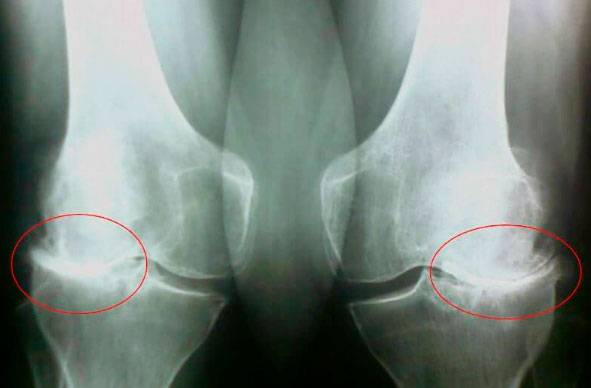

Погляньте на ці знімки, ви бачите, що на правому знімку суглобова щілина відсутня, кістки труться один об одного, викликаючи сильний біль. І цей процес дуже важко зупинити! Через пару років людина стане інвалідом і не зможе себе обслуговувати.